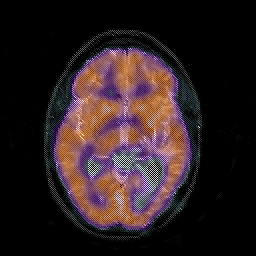

Glioblastoma multiforme overlay -- Slice #26

[Home][Help][Clinical][Tour 1][Tour 2][Tour 3] Slice 26